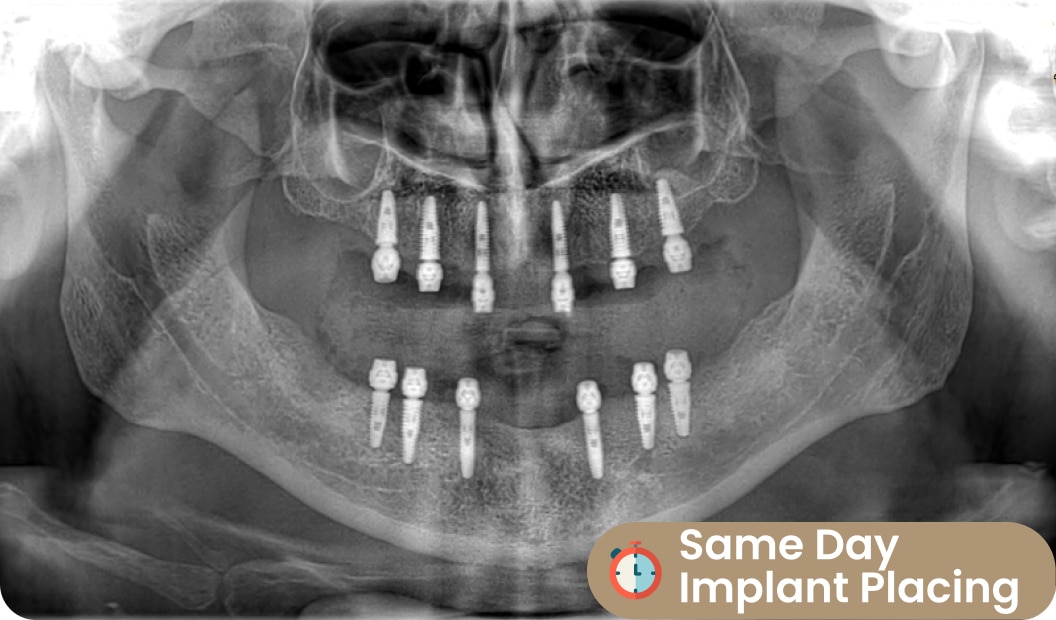

Implant Placing: Same Day (Day 1ST)

After 3D X-Ray process, Our dentists are starting to prepare teeth for the result. This steps can managed by several dentists in Dentafly. Cosmetic dentist shape teeth and prepare teeth for smile design process.

Cosmetic dentists measure mouth/teeth by 3D scanning. Lab. technicians prepare temporary teeth set in the same day. All temporary teeth produce by digital tech in DentaFly.